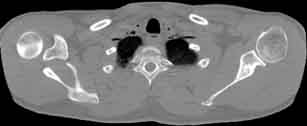

Visible Human male: Sectio transversalis 1305

CT